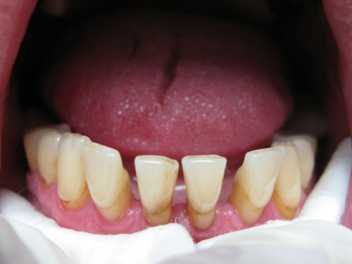

Главным симптомом пародонтита средней и тяжелой степени является шаткость зубов. Когда атрофия постигает костную ткань на ¼ длины корня зуба, развивается подвижность. При пародонтите оголяются шейки зубов, а рентген указывает на убыль кости. С появлением подвижности зубов, развитие атрофии еще больше ускоряется. В итоге зубы меняют свое месторасположение - расходятся, наклоняются в стороны. Для предотвращения подобного явления врач назначает процедуру шинирования. Кроме того, что шинирование стабилизирует положение зубных единиц, оно еще и способствует устранению воспаления десневой ткани.

Шинирование показано: при обнажении корней, нарушении положения зубов, а также их шаткости, при кровоточивости десен, наличии отложений на зубах и выраженных зубодесневых карманов. Благодаря процедуре создаются условия для равномерного распределения нагрузки, и в результате пациент может снова полноценно пережевывать пищу.

Под воздействием «силы жевания» уже подвижные зубы начинают сильно наклоняться и менять свое первоначальное положение. В результате в ротовой полости получается своеобразный веер из зубов. Чтобы остановить этот процесс применяют шинирование.

На атрофию костной ткани может указывать оголение шейки передних зубов. При отсутствии должного лечения такое состояние приводит к смещению зубного ряда. Остановить данный процесс может шинирование.